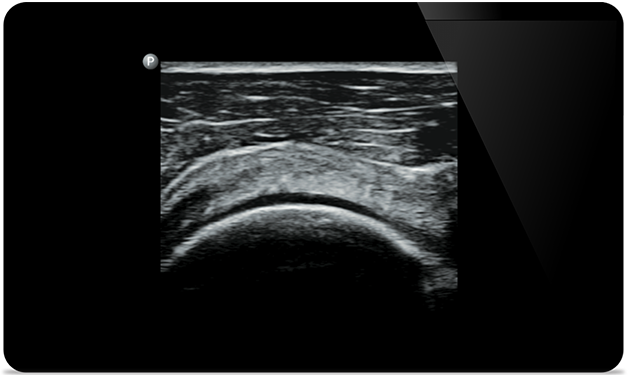

Punkcja stawu kolanowego

pod kontrolą ultrasonografii

Rozdarcie ścięgna mięśnia nadgrzebieniowego